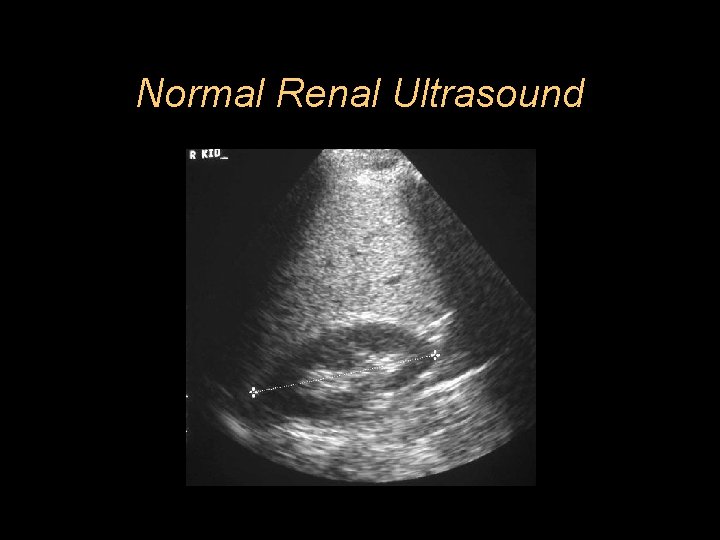

Normal Renal Ultrasound